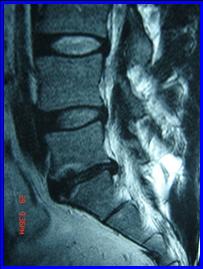

2.- Paciente de 45 años, con HNP L5 – S1 derecha que no respondió a tratamiento conservador, por 6 semanas, se realizó Nucleotomía Percutánea Automatizada con Apoyo Artroscópico, con lo que se resolvió el problema y volvió a trabajar a los 10 días.